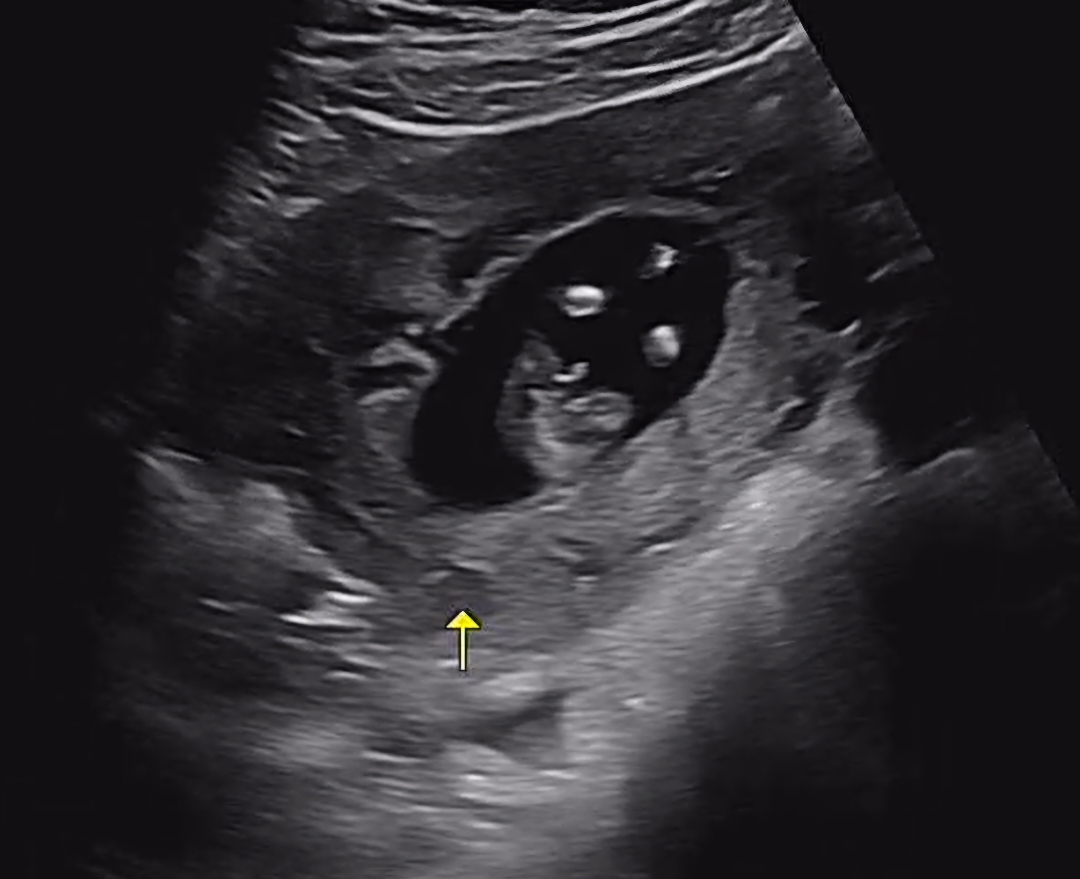

아들일까요 딸일까요? ㅎㅎ 12주차입니다